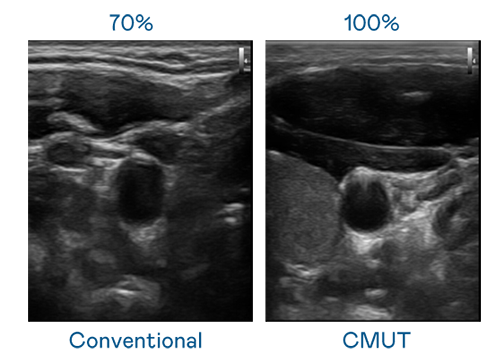

CMUT 技術是一種用電容式微機電元件來產生超音波訊號的技術。與傳統 PZT 壓電式技術相比,CMUT 頻寬增加 30%,更寬頻的超音波訊號讓影像解析度大幅提升,是實現高影像品質醫療超音波掃描、促進精準醫療發展的關鍵技術。

超音波影像的解析度高低,首先取決於探頭能發出的訊號頻寬。7790必发集团 CMUT 可提供高清晰的超音波訊號,提供高頻寬、高靈敏度、影像紋理細節更高的超音波影像,協助醫護人員縮短影像判讀時間及利用精準的醫療影像進行診斷。